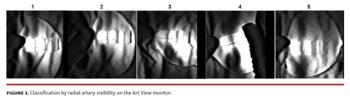

In this study, patients were divided according to the quality of RA visibility on the Art View monitor into 5 groups as follows: 5 (excellent) = constantly confirmed RA with a plastic plate; 4 (good) = confirmed RA with a plastic plate, with a quality between excellent and fair; 3 (fair) = confirmed RA with a plastic plate in the systolic phase, and slightly confirmed in the diastolic phase; 2 (not good) = confirmed RA with a plastic plate, with a quality between fair and poor; and 1 (poor) = slightly confirmed RA with a plastic plate in the systolic phase alone (Figure 3). Patients without RA confirmation on the Art View monitor and those in whom the puncture method or approach site were changed were excluded from this study. Benzethonium chloride (0.02%) was used as a colorless antiseptic solution to avoid permeability loss of near-infrared rays. The bodies of patients were covered with a surgical drape, except for the puncture site. Prior to RA puncture, 0.25-0.5 mL of 1.0% lidocaine was used as local infiltration anesthesia through a 27 G needle. The puncture site was compressed using a transparent, sterilized, plastic plate to prevent the venous flow as described above, and the RA was visualized on the Art View monitor. A black line drawn on the plate was aligned with the right RA. The right RA was punctured along the black line using a 20 G or 22 G indwelling needle with the Seldinger technique (Figure 4). Following penetration of the right RA by the indwelling needle, the inner needle was removed and the external sleeve was gradually pulled. Subsequently, the sheath-attached wire was crossed to confirm the backflow of the RA and advanced under x-ray fluoroscopic imaging to the brachial artery without any resistance. Finally, the 4 Fr sheath was inserted along its wire. RA puncture using the Art View was limited to 2 punctures. After unsuccessful RA puncture using the Art View device, the next step involved vascular ultrasound guiding, blind RA puncture, or change of approach site. Following insertion of the sheath, CAG was performed as usual. The aforementioned procedures were performed by a single cardiologist to avoid procedural bias.